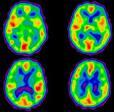

“We are pleased to collaborate with the International Partnership for Critical Markers of Disease on this important meeting,” said Michael Graham, M.D., Ph.D., SNM president-elect and director of nuclear medicine at the University of Iowa Carver College of Medicine. “New developments in molecular imaging technologies are dramatically improving the ways in which cardiovascular disease, neurological disorders and cancer are diagnosed and treated. It is essential that we work together as a scientific community to facilitate personalized medicine through the development of advanced imaging techniques and new radiopharmaceuticals that will enable physicians to determine early on the precise location of disease, and evaluate and monitor the effectiveness of therapy.”